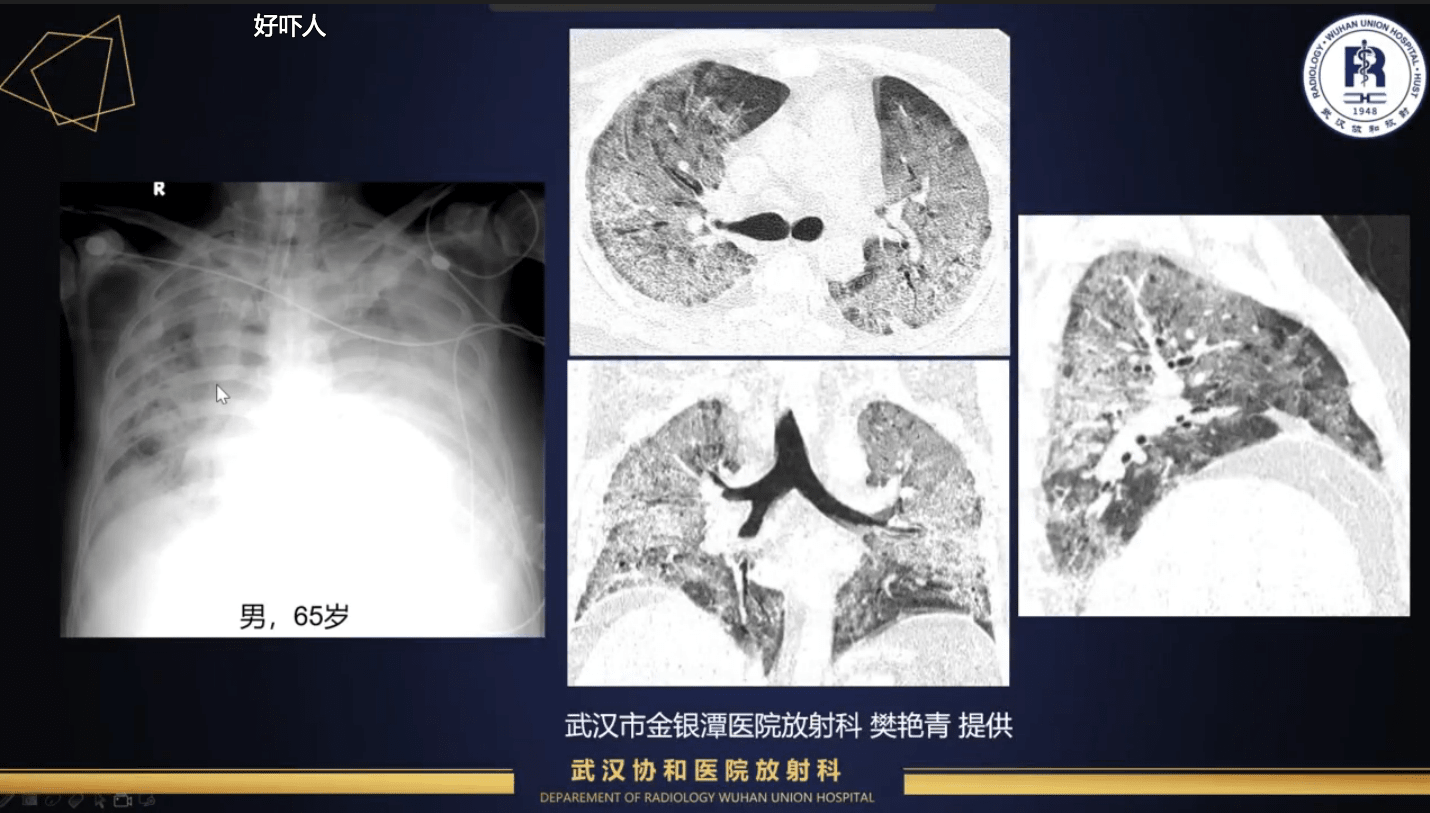

武汉金银潭医院樊艳青主任曾说过一句:“我告诉自己不要流泪,眼睛要用来看片子”。放射科医生在疫情期间的工作压力可想而知。

武汉协和医院放射科副主任史河水教授表示,**现在的工作强度是往年春节同期的3~4倍,而且每天肺部CT扫描占全天所有CT检查的90%**。同时,放射科医师可以通过制作教学课件、肺CT检查的科普读物,提高广大放射科医师对新冠肺炎CT征象的认识、老百姓对CT检查的了解,同样也是在为抗击疫情做贡献。武汉是肺炎疫情的核心区域,国际国内学术界也十分关注,希望武汉的医生能借助国内外的学术平台,及时交流经验,科学地抗击疫病。

2月12日,新增新冠肺炎病例一下子上涨到了14840例。这是因为,湖北省将临床诊断病例数纳入了确诊病例数。根据第五版诊疗方案的表述,疑似病例具有肺炎影像学特征者,为临床诊断病例。新增案例的增长,从一定程度上说明了影像学在这次肺炎疫情中所发挥的价值。总的来说,新冠肺炎的一大特点是“快”。2月17日,国家卫健委医政医管局监察专员郭燕红表示,目前新冠肺炎患者从发病到确诊平均用时4.95天。

史河水主任表示,新冠肺炎患者肺内病变多,变化快,而且有些病变不易与其他感染或非感染性病变鉴别。医生凭借肉眼,要做出准确的定性诊断与定量评价,费时而且有难度。所以,很多医疗AI公司提出,在此前AI产品在肺部疾病解决方案的基础上,协助医生对新冠肺炎的诊断和疗效评价进行预估。总体来说,我个人认为AI在新冠肺炎的定量、定性评价方面,能提高医生的诊断效率。疫情爆发期过后,如何将散发新冠肺炎与其他病毒性肺炎等肺部病变进行鉴别,对放射科医生也是一种挑战,AI在这些方面也可以做一些工作。我们也需要这样一个工具,帮助我们更高效高质量地完成工作